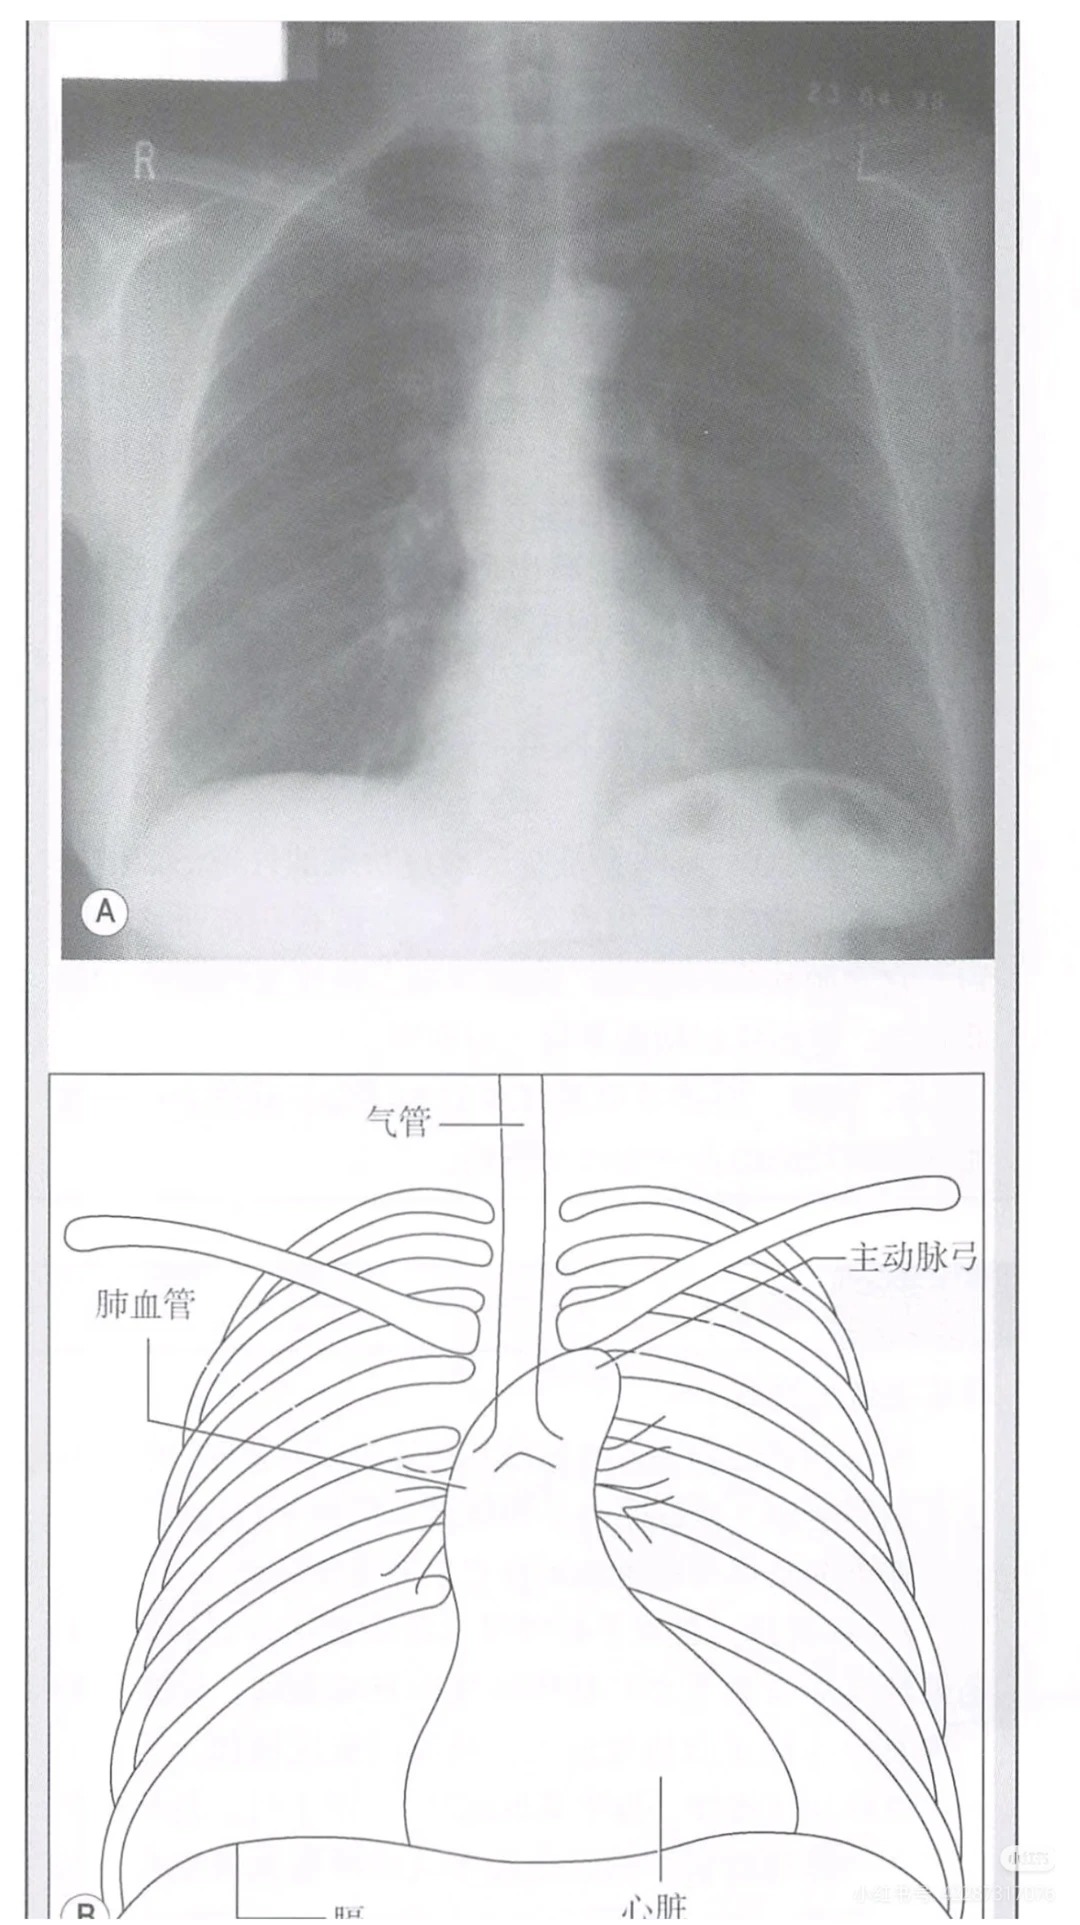

4. 超清图文,学习不枯燥:全套采用超清印刷,配有大量清晰的解剖示意图、病理图片、诊疗流程图,将复杂的医学知识、抽象的生理机制、繁琐的诊疗流程直观呈现,打破传统教材的枯燥感,让学习更轻松、记忆更深刻,适配医学生长时间学习需求。